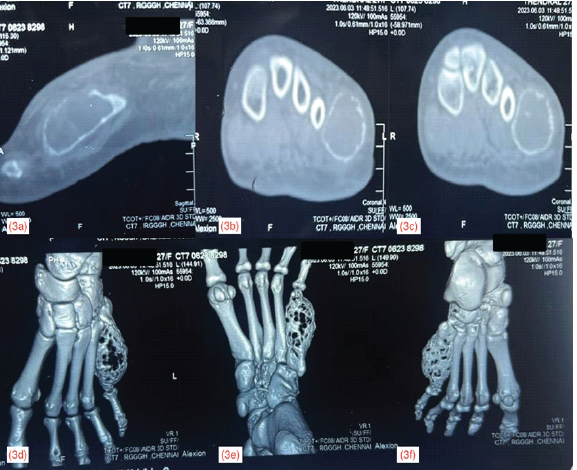

Computed tomography scan showed an expansile lytic lesion with well-defined margins and internal septations involving the shaft of left 5th metatarsal, without involvement of the proximal and distal epiphysis (Fig. 3).

Figure 3: Computed tomography image of lesion in sagittal (a), axial cut (b and c), and 3D-reconstruction (d-f)